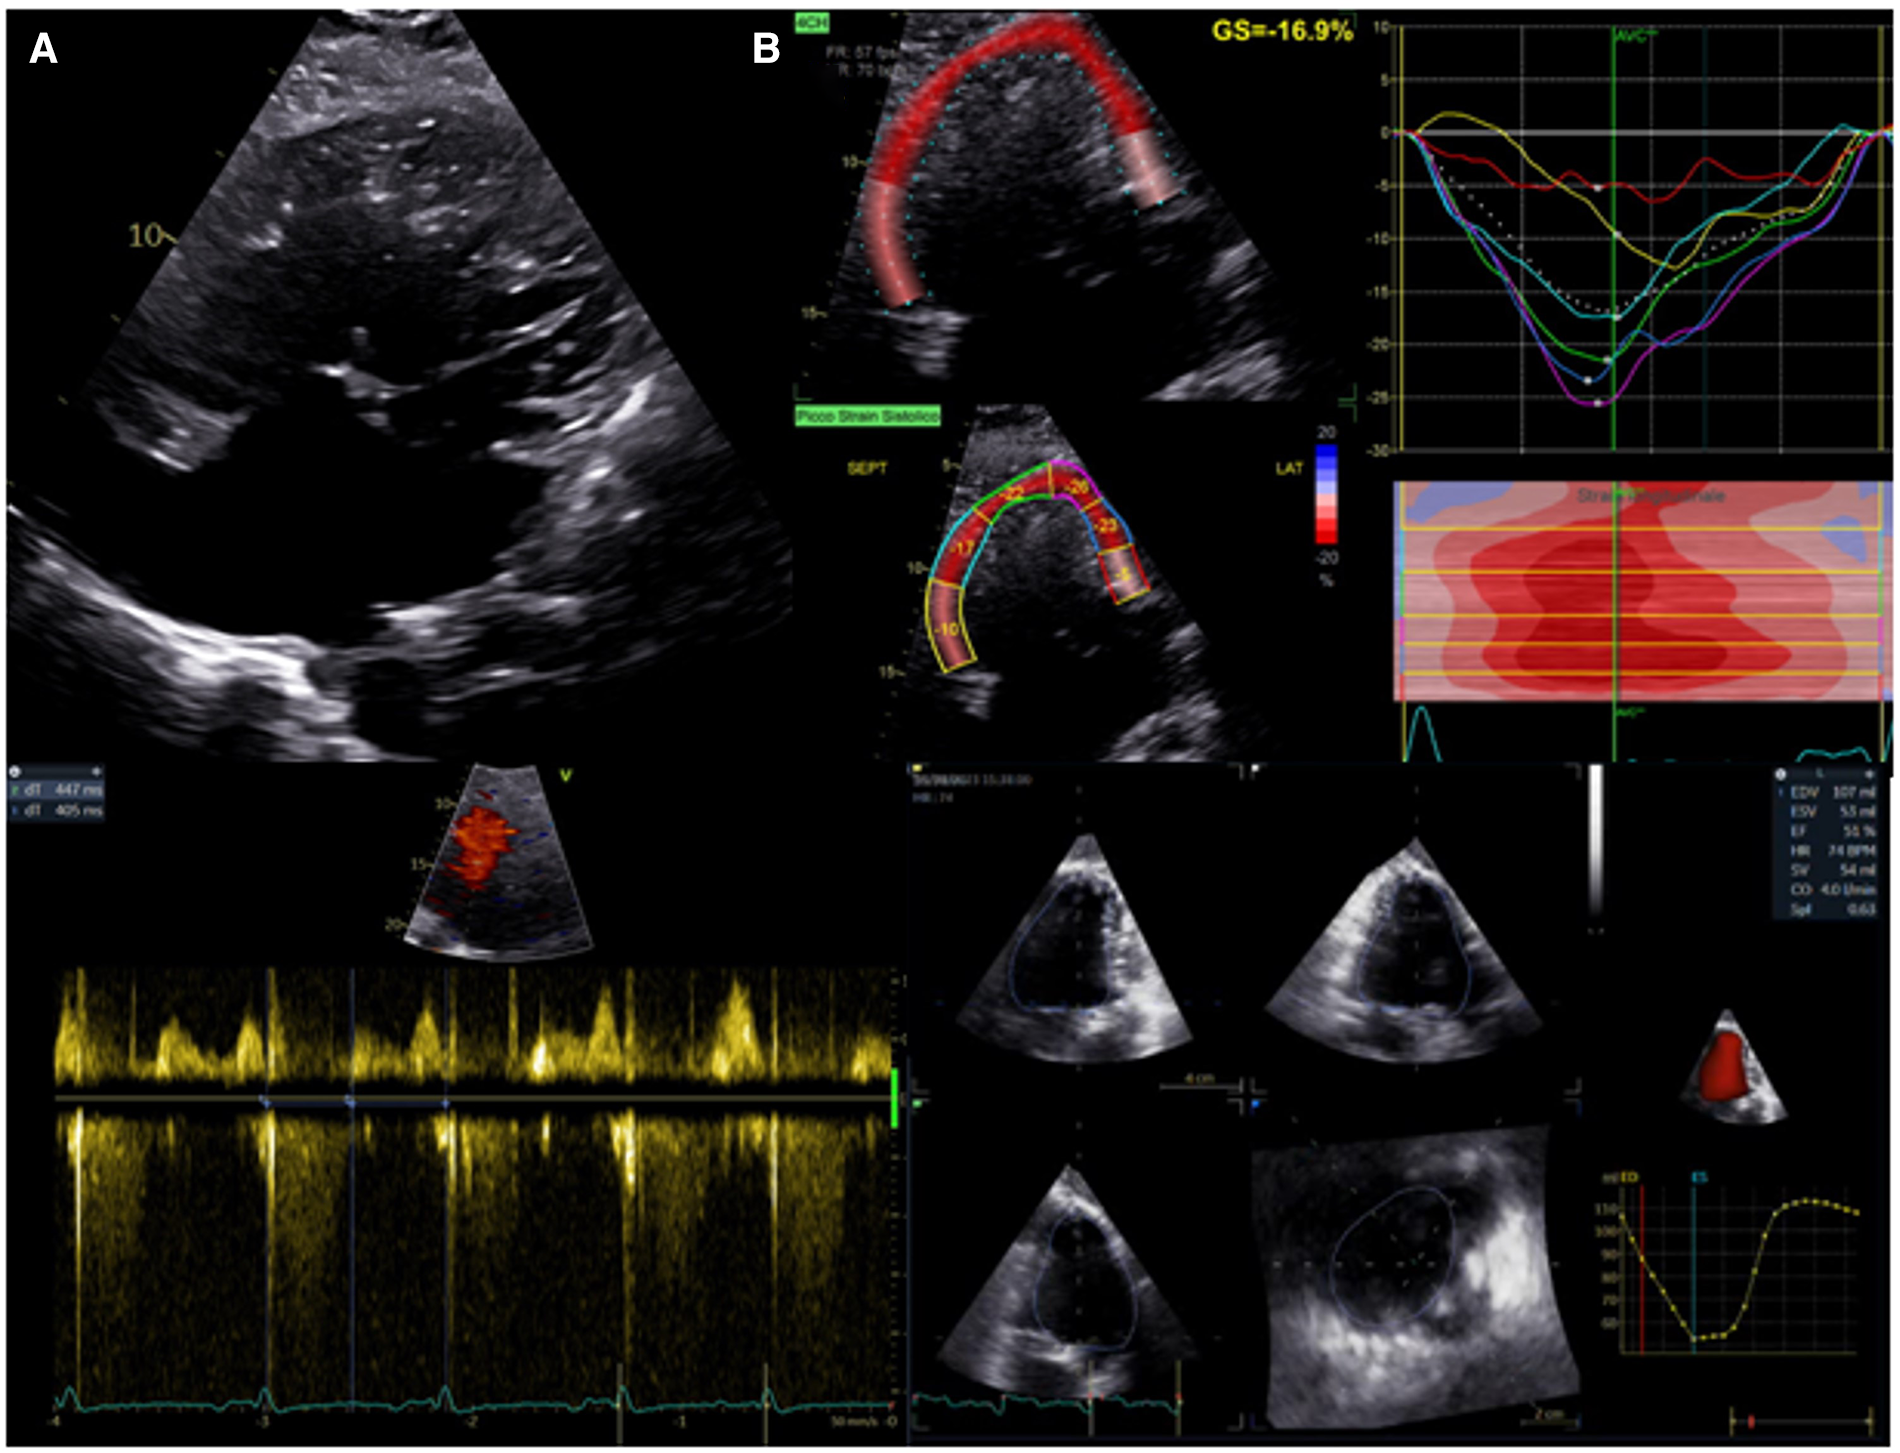

In the presence of a univentricular heart with left morphology, the most common approach to estimate systolic function is the biplane Simpson's method. Even though this method is load-dependent and influenced by geometry, it has a moderate correlation with MRI measurements and reasonable reliability (86). Even more challenging can be the evaluation of a morphological right single ventricle. FAC is a simple geometric method, but its accuracy can be limited by the complex anatomical geometry and the high inter and intra-observer variability (87). Of note, these measurements have no precise normal values for univentricular hearts, but they are valuable when evaluated in the longitudinal follow-up. The atrioventricular systolic to diastolic duration ratio has been used to evaluate ventricular performance without anatomical assumptions. Cordina et al. (88) demonstrated that a value >1.1 independently predicts mortality in adult patients with Fontan circulation. STE has emerged as a valid and reliable method for assessing single-ventricle function without geometric assumptions or the effect of acute preload (89). When the GLS is evaluated serially in the follow-up of children with hypoplastic left heart syndrome, it has been demonstrated to predict ventricular dysfunction leading to need for transplantation or death (87). A recent study (90) demonstrated the different value of longitudinal strain related to the different univentricular morphology. Single right heart has shown lower longitudinal strain than biventricular and single left heart morphology, underscoring a worse morbidity associated with this subgroup. STE has also been used to demonstrate a dyssynchronous pattern in patients with Fontan circulation. The dyssynchronous segments showed an early shortening (“flash”), followed by a systolic stretching; while segments with conduction delay showed early stretching, followed by delayed contraction. A recent study (91) demonstrated this dyssynchronous pattern was associated with a worse outcome in patients with Fontan circulation. 3D echocardiography allows the evaluation of univentricular dimensions and function without geometrical assumptions. The evaluation of three-dimensional ejection fraction and volume appears feasible with a good correlation with CMR, although it is noteworthy to underscore the underestimation of measurements in comparison with CMR (92) (Figure 3).

Figure 3

Evaluation of systolic function in patients with univentricular heart after fontan procedure. (A) Upper panel: apical 2D view. Lower left panel: atrioventricular systolic to diastolic duration ratio. (B) Upper panel: univentricular speckle tracking analysis. Lower right panel: 3D ejection fraction evaluation.